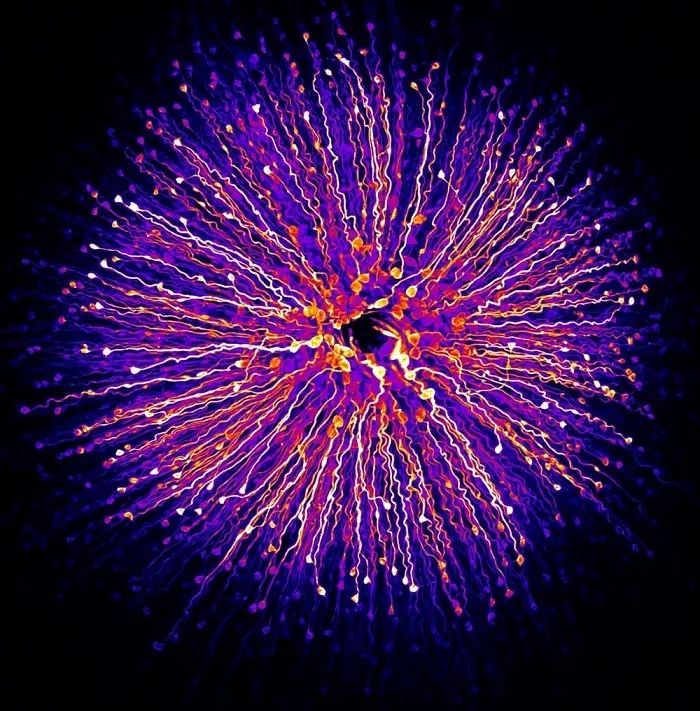

人类泪滴

第 7 名:人类泪滴(Norm Barker / 摄)Norm Barker来自约翰霍普金斯医学院病理学与艺术系